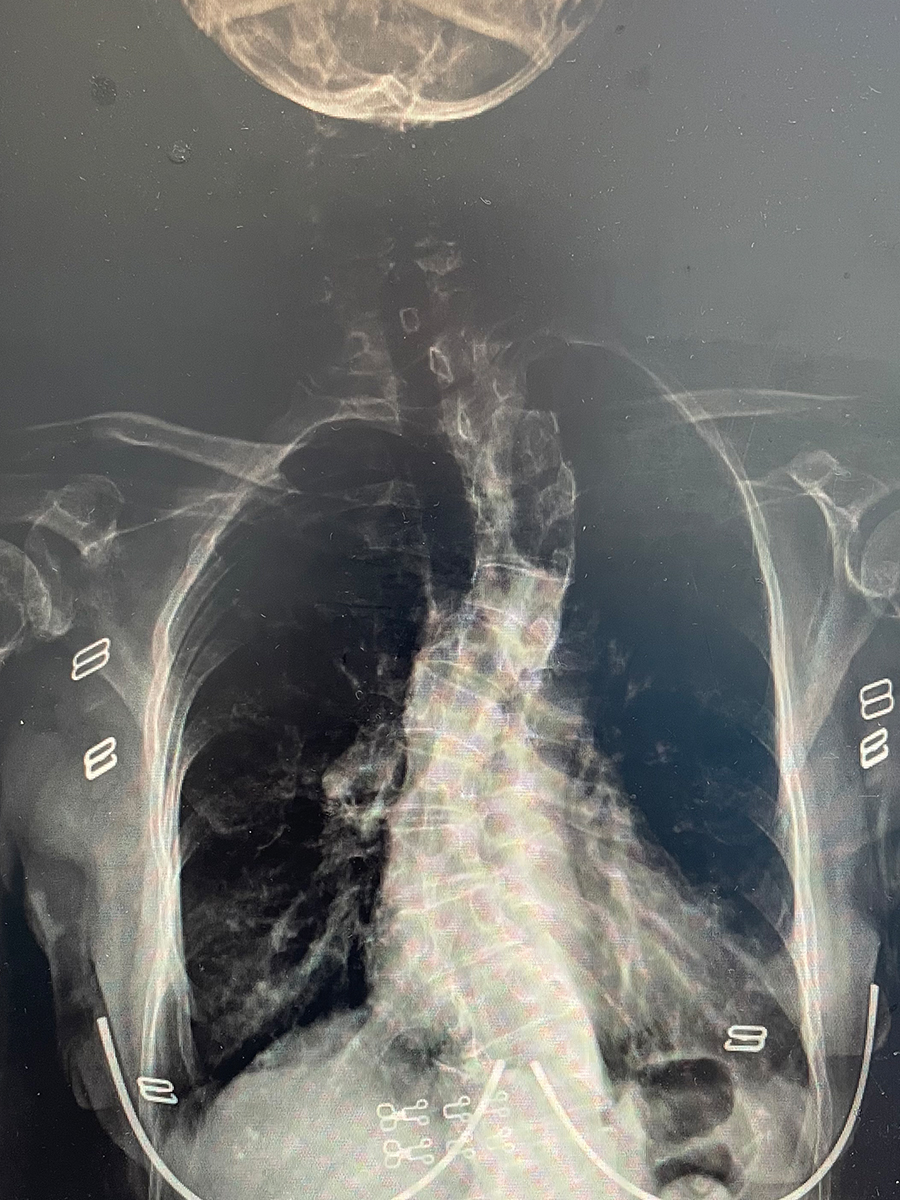

重度脊柱侧凸讨论 [精华] [病例帖]

图片尺寸2448x3264